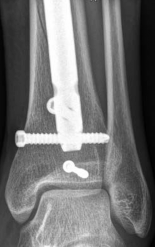

Once reduced, the articular block is secured with independent 3.5 mm or 4.0 mm partially threaded cancellous lag screws. These screws must be placed strategically—typically in the anterior or posterior half of the epiphysis—to leave the central medullary canal completely unobstructed for the nail.

Image

Fibular Fixation Strategy

The role of fibular fixation in distal tibia fractures remains a topic of academic debate, but in the context of intramedullary nailing, it is often a highly valuable adjunct. Plating the fibula restores the length of the lateral column and corrects rotational malalignment, effectively converting a highly unstable distal tibia fracture into a more manageable, length-stable pattern.

Fibular fixation is typically performed prior to tibial nailing. An open reduction and internal fixation utilizing a one-third tubular plate or anatomic distal fibula plate is standard. By stabilizing the fibula, the tendency for the distal tibia to drift into valgus during nail insertion is significantly mitigated.